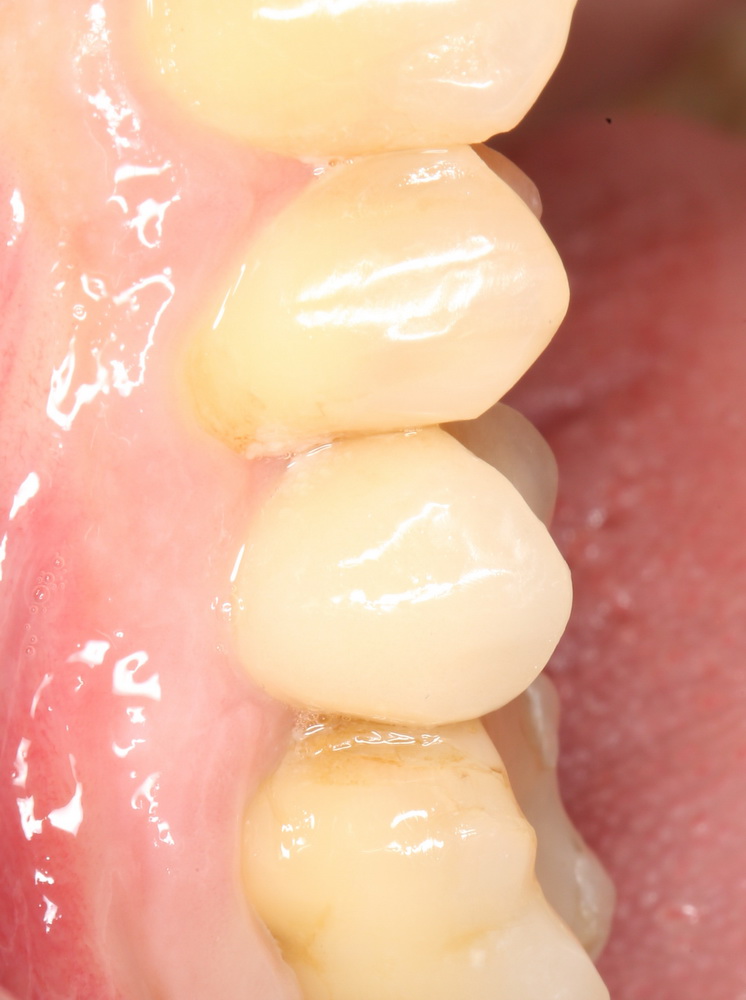

Вот клиническая картина и рентгенологический контроль через 2,5 года после имплантации и протезирования:

Данные конусно-лучевой компьютерной томографии области имплантации через 2,5 года выглядят более интересными:

Как видите, под приемлемыми объёмами и состоянием десны в области имплантатов скрывается надёжный фундамент — восстановленная и сохраненная с помощью аугментации костная ткань, состояние которой за два с половиной года только улучшилось.

С точки зрения функционала, Мария не чувствует принципиальной разницы между естественными здоровыми зубами и коронками на имплантатах (последние она находит «более симпатичными») По её словам, она и думать забыла об имплантатах, а прошлые мучения с зубами кажутся ей «ночным кошмаром».